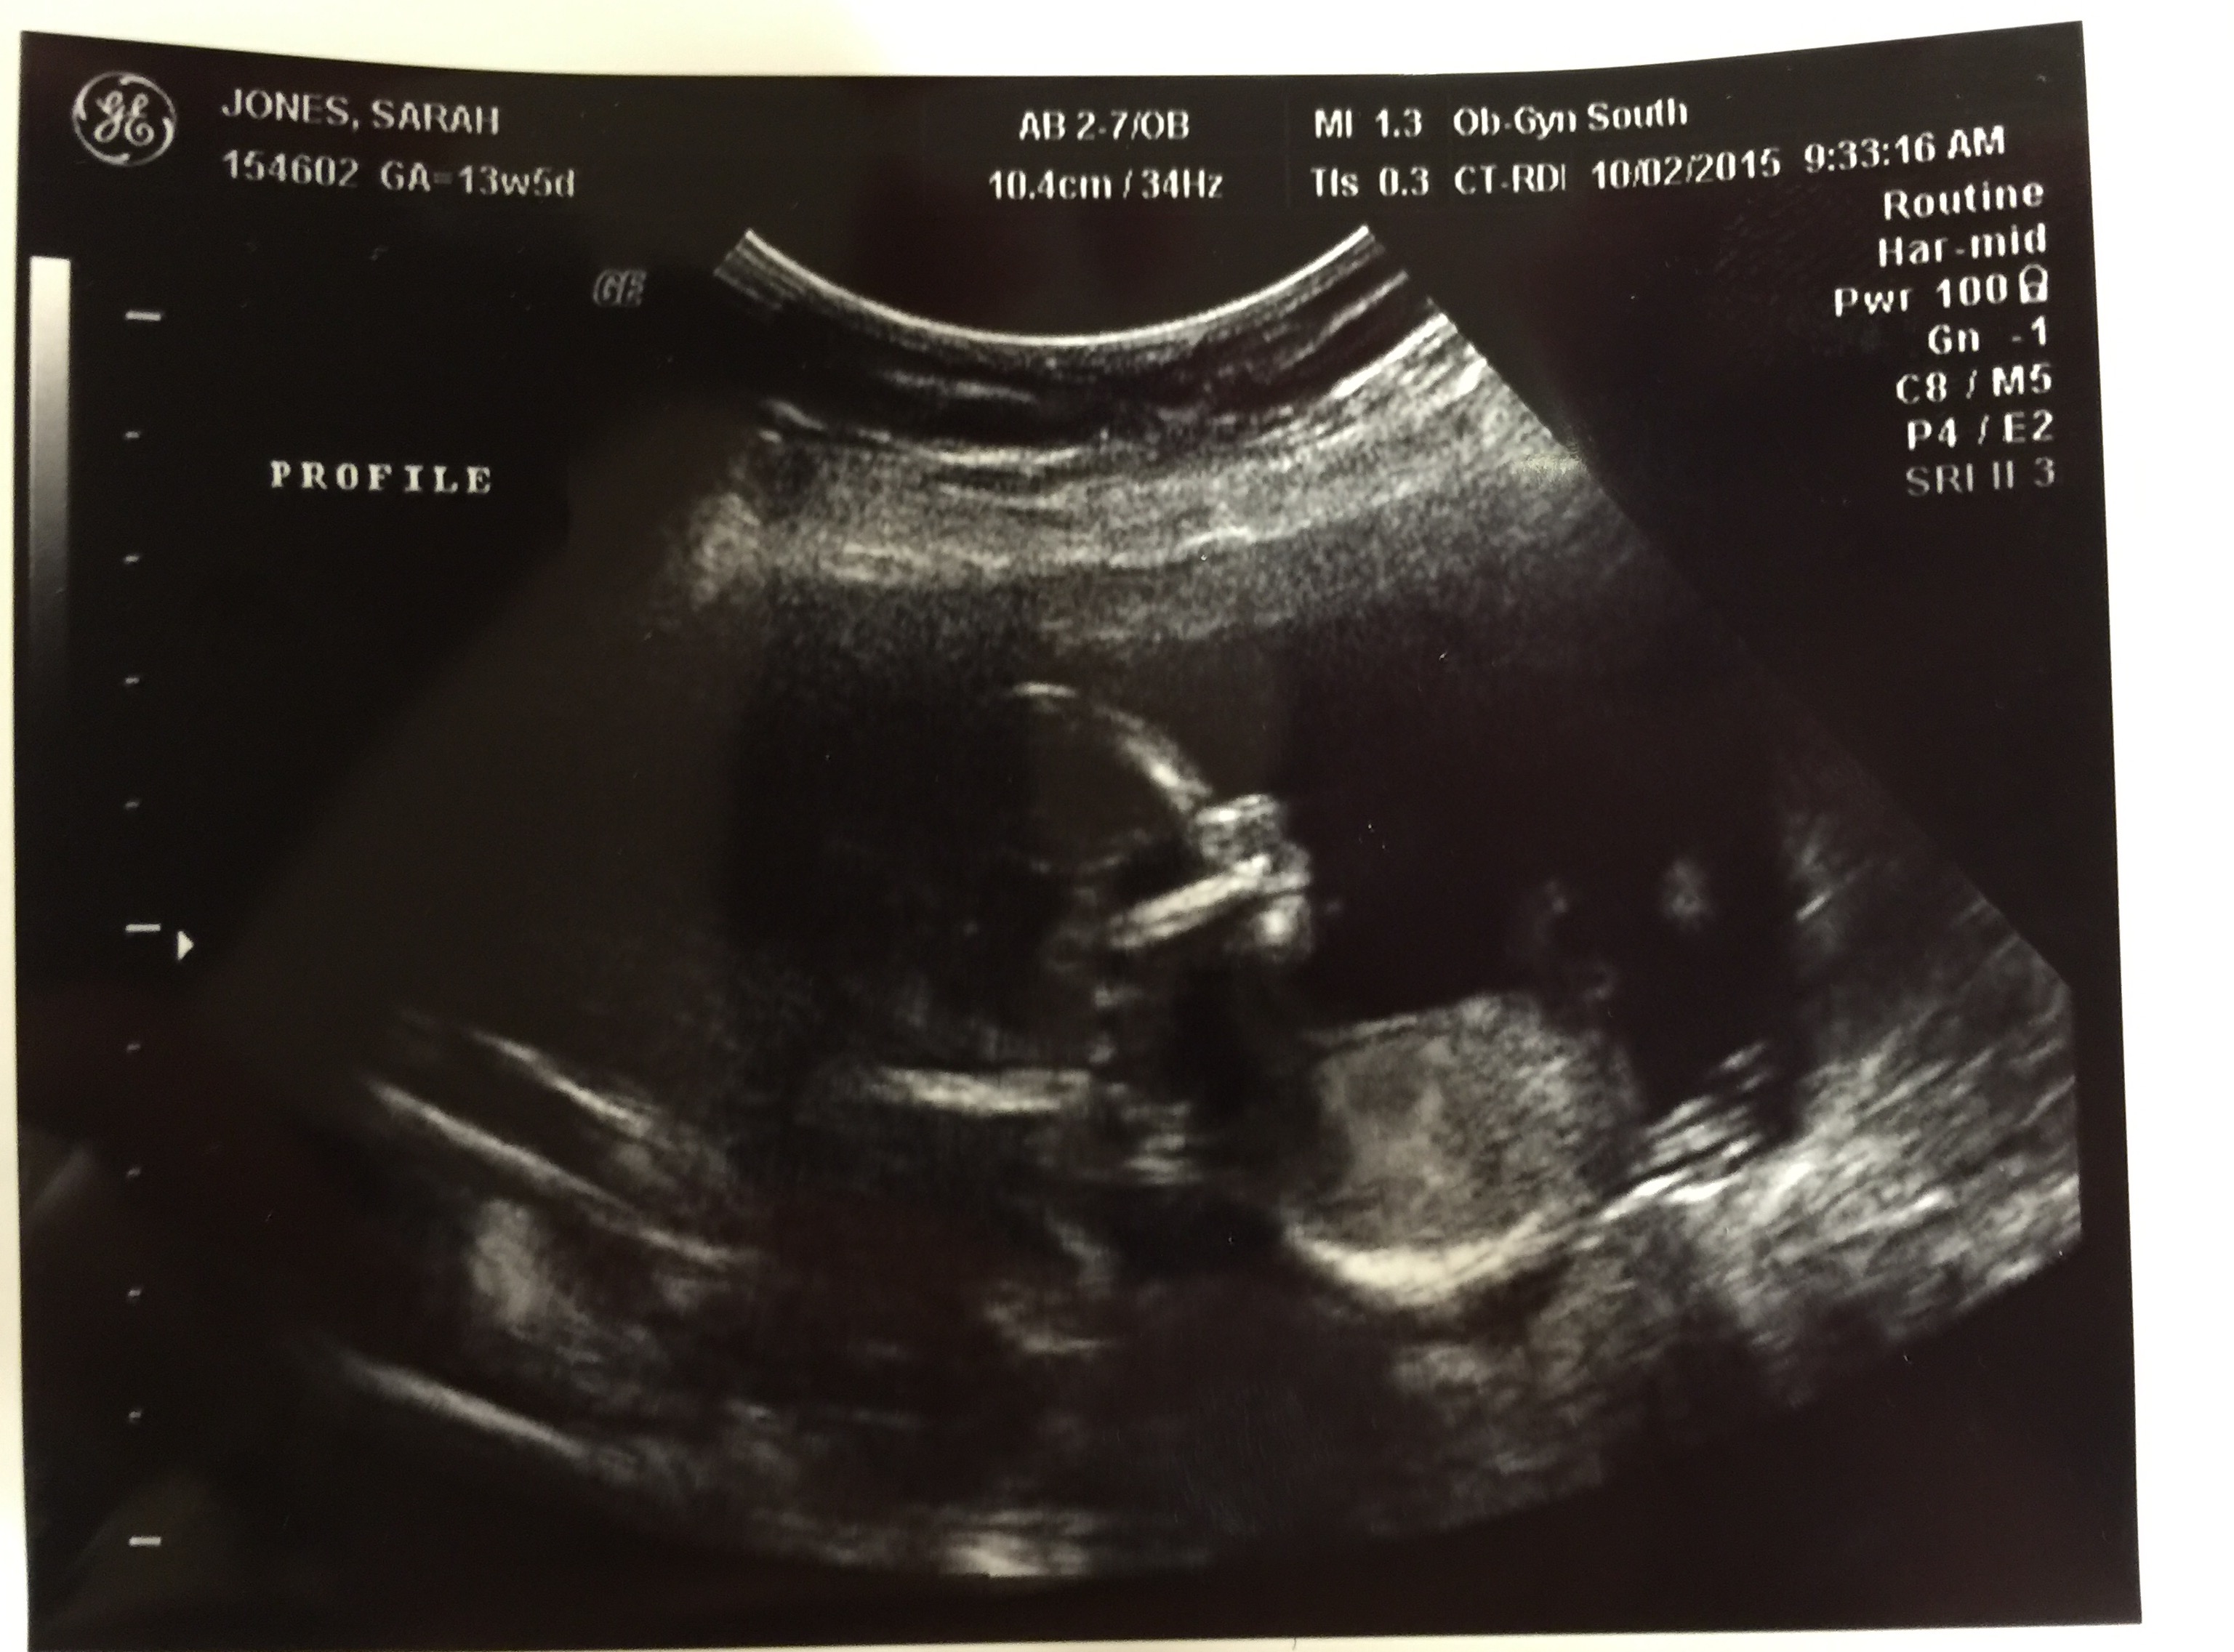

13w5d in the photo